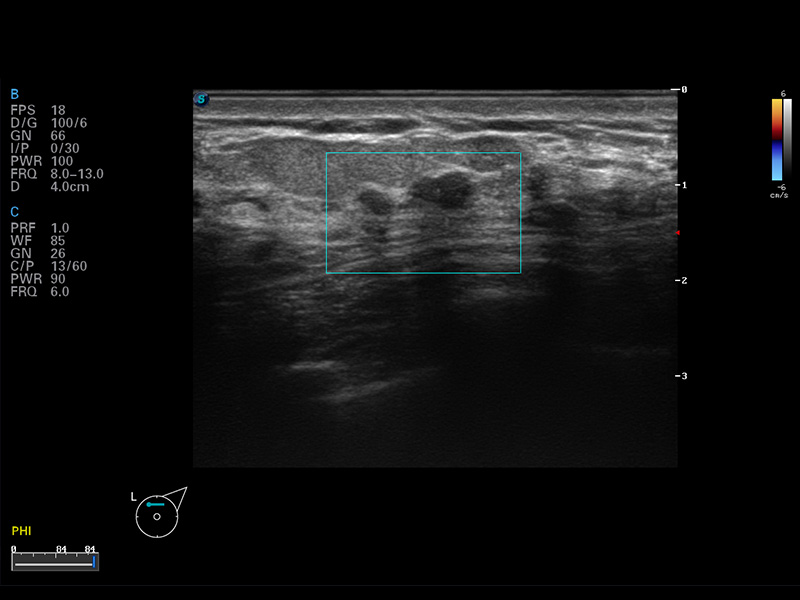

S8 EXP便携式彩色多普勒超声诊断仪是银河集团官网研发的高端全身应用型便携彩超。高通道的VIS平台融合可视化(Visual)、智能化(Intelligent)和人性化(Smart)的特点,配以银河集团官网自主研发生产的探头大家族,使您能够快速、准确的获得病人信息,提高工作效率的同时减轻疲劳。

成像技术

多波束形成器

μ-Scan微米成像

谐波成像

实时宽景成像

空间复合成像

3D/4D成像